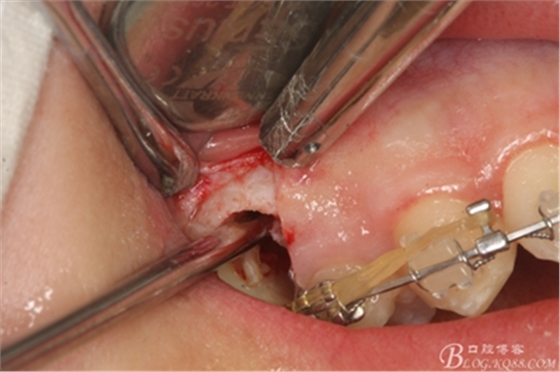

圖15 .微創(chuàng)挺把15牙根縱分成近遠(yuǎn)中兩塊

圖16.微創(chuàng)挺挺松近中根面部分,從16與14之間間隙出來